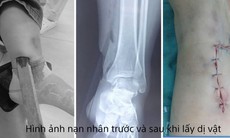

Bác sĩ Nguyễn Mạnh Thưởng, Trưởng Khoa Ngoại – Gây mê hồi sức cho biết, bệnh nhân B.T.Đ. (15 tuổi, trú phường Đồng Thuận, tỉnh Quảng Trị) vào viện với tâm lý hoảng sợ khi móc câu 3 tiêu cắm sâu vào da ở phần đỉnh đầu khiến chảy máu và đau nhiều.

Khai thác nhanh, bệnh nhân cho biết trong lúc đi câu cùng bạn, do không giữ khoảng cách an toàn nên bị lưỡi câu móc vào đầu.

"Lưỡi câu cắm xuyên da ở phần đỉnh đầu, may mắn không gây hại mạch máu, dây thần kinh quan trọng. Đánh giá tình trạng, chúng tôi gây tê tại chỗ để thực hiện thủ thuật lấy móc câu ra an toàn. Bác sĩ cũng khuyến cáo bệnh nhân tiêm vaccine phòng uốn ván để tránh nguy cơ biến chứng đáng tiếc", bác sĩ Thưởng thông tin.